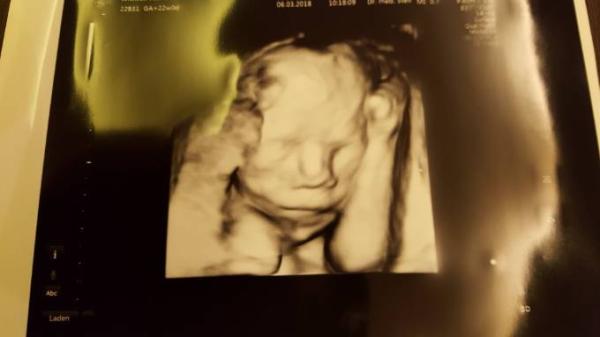

Auch bei uns ist soweit alles gut und hab sogar was süßes mitgebracht. Schaut mal...

Bild zu Zurück von FD - Forum für Juli - Mamis

Ach Gott sind das süße Bilder, schon so real... ein richtiges Baby....Wahnsinn. So toll das alles okay ist, was für ein schönes Geschenk

Im Moment finde ich 3D-Aufnahmen irgendwie noch sehr gruselig... Gut, dass ich keine werde machen lassen. Aus Jux nenne ich mein Würmchen auch manchmal "kleines Alien". Aber schön, dass bei euch alles gut ist